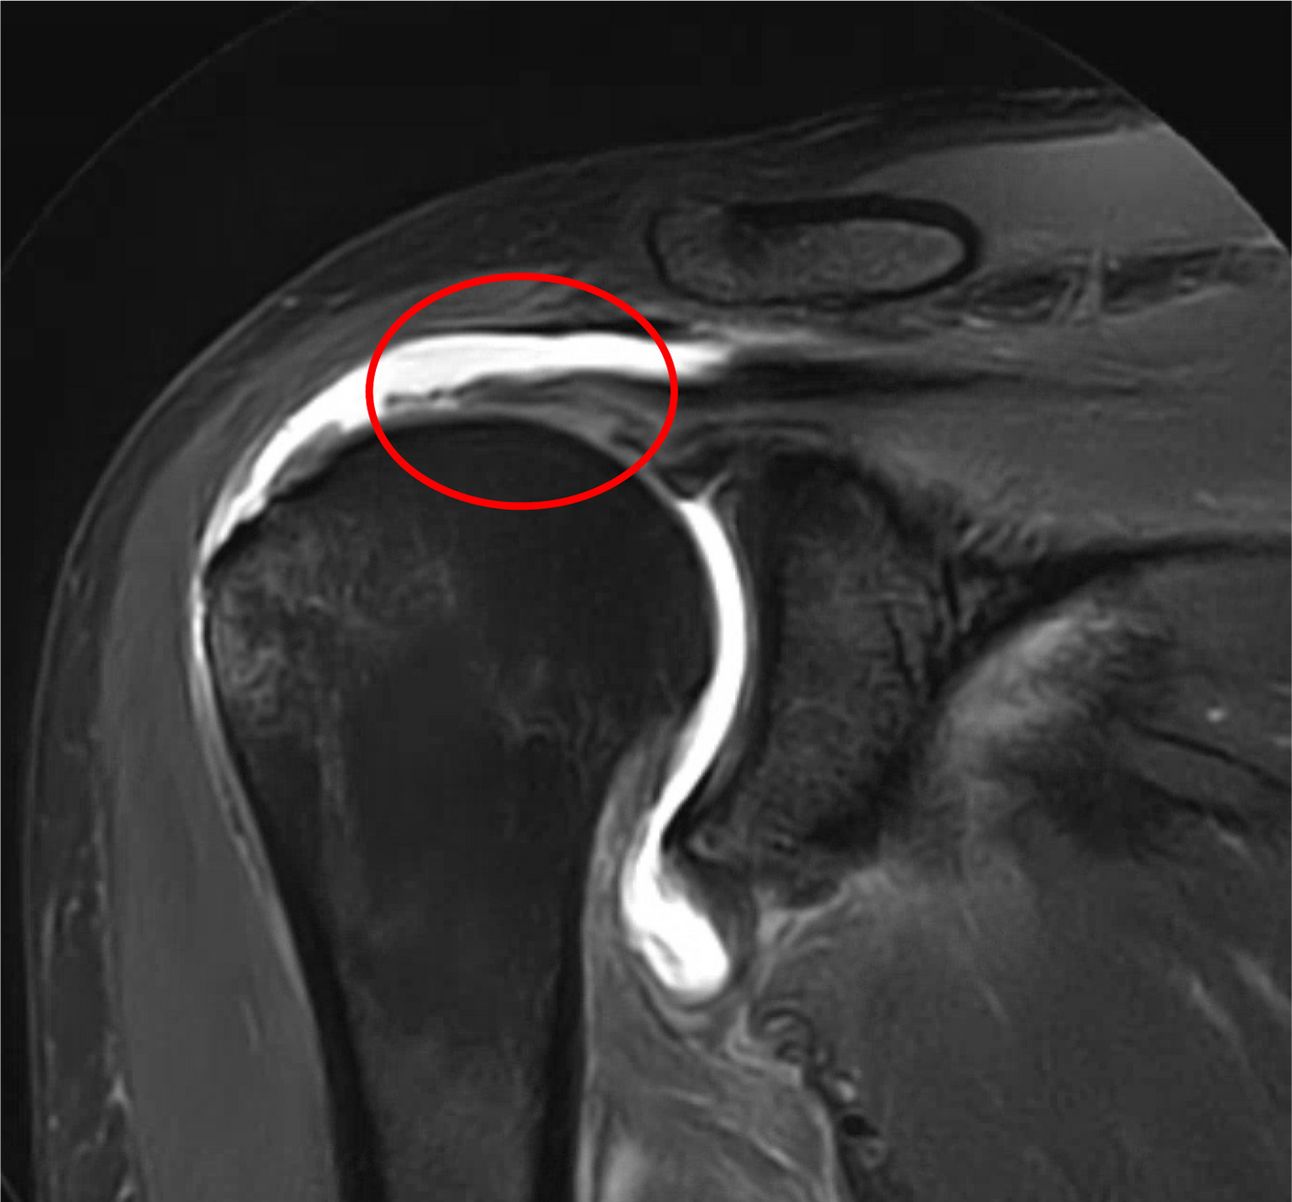

Abnormal MRI: Rotator Cuff Tear

Notice the bright white fluid filling the gap in the band of the tendon.

A-P view of a shoulder MRI with a Rotator Cuff Tear

Rotator Cuff Tendons

Appear as dark bands above the ball of the shoulder

Should be continuous without gaps; tears will show up as bright white areas which indicate fluid/swelling